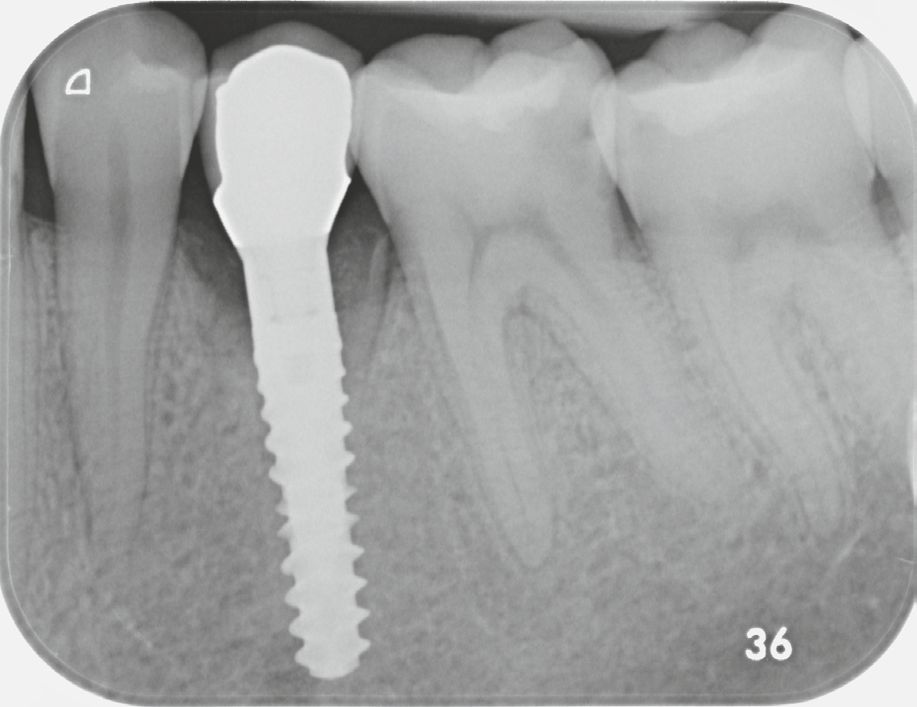

Fig. 6: Postoperative X-ray image of region 34, condition after immediate implantation. |

Figure 10: X-ray image after prosthetic restoration. |

After osteotomy, I placed a 3.75 mm diameter implant, filled the gap between implant and root surface with allogenic bone substitute, inserted a provisional, and later restored with an aesthetic ceramic crown.